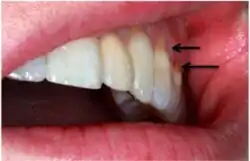

When looking at abfraction lesions there are generally three shapes in which they appear, appearing as either wedge, saucer or mixed patterns.[6] Wedge and saucer shaped lesions are the most common, whereas mixed lesions are less frequently identified in the oral cavity.[6] In reference to figure 1, wedge shaped lesions have the sharpest internal line angles and saucer/mixed shaped lesions are either smooth internally, or a variety.